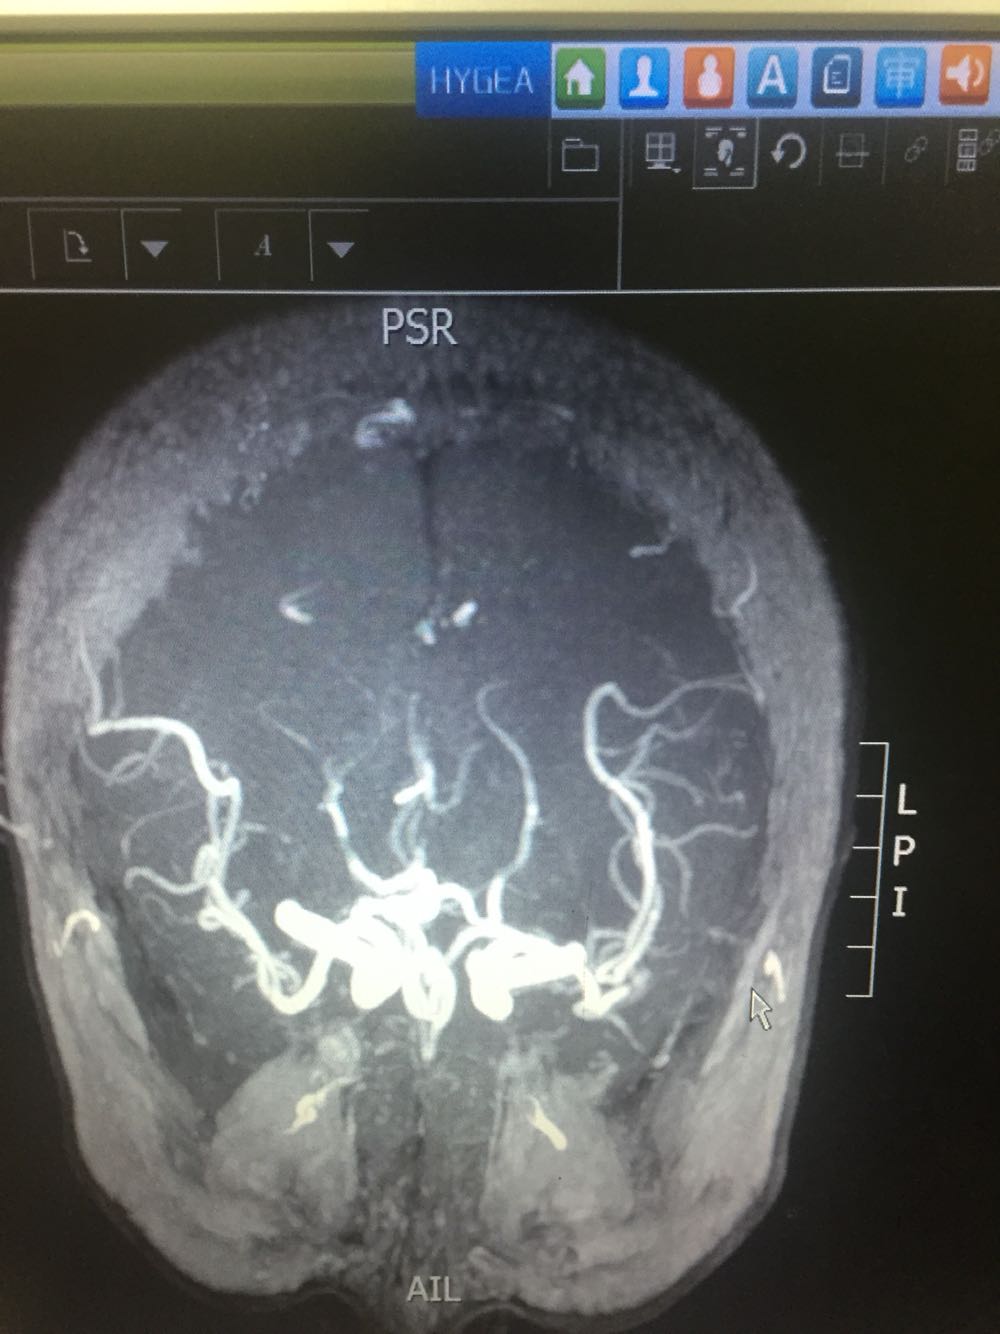

患者于入院后第二日晨起时突发左侧肢体无力伴抽搐发作,查体:神志模糊,言语含糊,双侧瞳孔等大同圆,对光发射存在,左侧肢体肌力3级,左下肢Babinski(+)Chaddock(+) 不伴有尿便失禁。给予安定肌肉注射,急检血凝及头CT。血凝、头CT回报未见明显异常。患者发病1.5小时与家属沟通建议溶栓治疗,家属同意。患者体重约75kg。给予6mg爱通立静脉推注,随后60分钟内爱通立54mg静脉滴注。患者恢复良好,肌力恢复正常。查头DWI示:右侧侧脑室后脚可疑新发梗死。